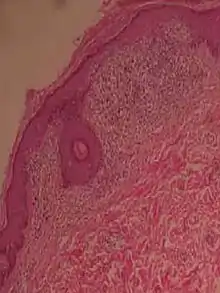

Psoriaform dermatitis

Examining multiple deeper levels is recommended if initial cuts do not correlate well with the clinical history.[2]

Psoriaform dermatitis typically displays:[2]

- Regular epidermal hyperplasia, elongation of the rete ridges, hyperkeratosis, and parakeratosis.

- Usually:A superficial perivascular inflammatory infiltrate

- Often: Thinning of epidermal cells overlying the tips of dermal papillae (suprapapillary plates), and dilated, tortuous blood vessels within these papillae

Further histopathologic diagnosis is performed by the following parameters:

| Condition | Hyperkeratosis | Parakeratosis | Acanthosis | Suprapapillary plate | Granular cell layer changes | Spinous cell layer changes | Basal cell layer changes | Other distinctive feature | Micrograph | Photograph |

|---|---|---|---|---|---|---|---|---|---|---|

| Psoriasis | Present | Diffuse | Regular | Thin | Decreased or absent | Increased mitoses; minimal spongiosis Clubbed rete pegs[12][13] | Absent |

|

| |

| Psoriasiform drug reaction | Present | Focal | Regular and irregular | Normal or thick | Normal | Spongiosis; eosinophilic infiltrate | Inflammatory cells; Civatte bodies | |||

| Chronic allergic/contact and atopic dermatitis | Present | Focal; crust may be present | Irregular | Normal or thick | Normal | Spongiosis; eosinophilic infiltrate | Absent | |||

| Fungal infection | Compact | Focal; crust may be present | Irregular | Normal or thick | Normal | Occasional neutrophiles; | Absent | |||

| Lichen simplex chronicus | Present | Focal; thick crust | Regular or irregular | Thin or thick | Thickened; hypergranulosis | ±minimal inflammatory infiltrate | Absent | |||

| Scabies | Present | Focal or diffuse | Irregular | Normal or thick | Normal | Inflammatory infiltrate; eosinophilic spongiosis | Absent | |||

| Seborrheic dermatitis and HIV dermatitis | Present | Focal | Irregular | Normal or thick | Normal | Spongiosis; lymphocytic and neutrophilic infiltrate | Absent | |||

| Pityriasis rubra pilaris | Compact | Shoulder parakeratosis;[notes 3] alternating orthokeratosis and parakeratosis | Regular or irregular | Normal or thick | Normal | Spongiosis; lymphocytic infiltrate; rare acantholysis | Occasional vacuolar change | |||

| Pityriasis rosea | Present | Focal | Irregular | Normal or thick | Normal | Small foci of spongiosis; lymphocytic infiltrate | Occasional necrotic keratinocytes | |||

| Syphilis | Present | Focal | Regular or irregular | Normal or thick | Normal | Lymphocytes and neutrophils | Interface change | |||

| Pityriasis lichenoides chronica | Present | Caps of parakeratosis | Irregular | Normal | Normal | Mild spongiosis, lymphocytic infiltrate; necrotic keratinocytes | Necrotic keratinocytes | |||

| Mycosis fungoides | Present | Focal | Regular or irregular | Normal | Normal | Minimal or no spongiosis; ±Pautrier microabscess | Atypical lymphoid cells lining the dermo–epidermal junction |  Pautrier microabscesses |